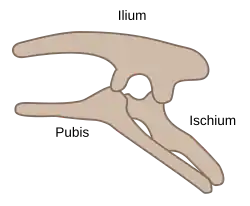

Structure

There are three bones of the os coxae (hip bone) that come together to form the acetabulum. Contributing a little more than two-fifths of the structure is the ischium, which provides lower and side boundaries to the acetabulum. The ilium forms the upper boundary, providing a little less than two-fifths of the structure of the acetabulum. The rest is formed by the pubis, near the midline.

In infants and children, a Y-shaped epiphyseal plate called the triradiate cartilage joins the ilium, ischium, and pubis. This cartilage ossifies as the child grows.[10]